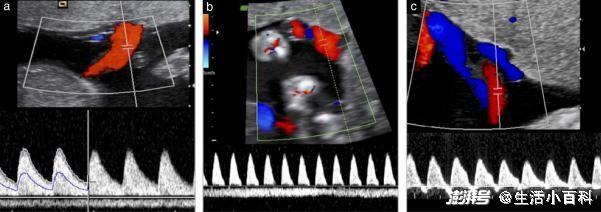

超声多普勒血流检测还可以对生长受限胎儿的脐动脉血流、脐静脉血流、大脑中动脉血流、静脉导管血流等进行评估。这些血流指标非常重要,在产科医师制定处理决策中占据重要地位,合理运用可以有效降低因胎儿生长受限导致的围产儿病率及死亡率,是胎儿生长受限最重要的监测方法,对于生长受限的胎儿,如果发现其脐动脉搏动指数正常,建议每两周复查一次。